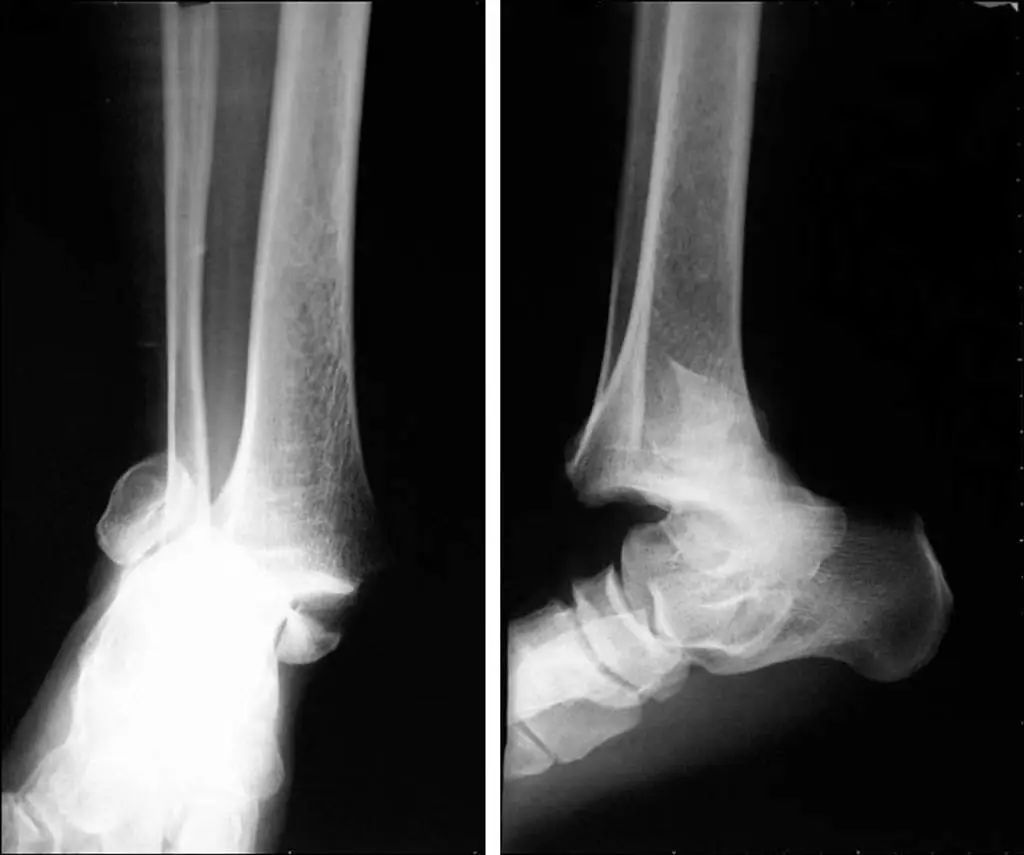

При серьезном повреждении голеностопного сустава внутренняя и внешняя лодыжки и таранная кость смещаются на 11 различных градусов (рис. 11).Статические рентгенограммы не точно отражают стабильность голеностопного сустава.Стресс-рентгенограммы и МРТ могут улучшить оценку стабильности голеностопного сустава и повреждения связок (рис. 12).

Рис. 11. Смещение перелома, по-видимому, в сочетании с вывихом.

Рисунок 12. Рентгенограмма под нагрузкой (разрыв треугольной связки)